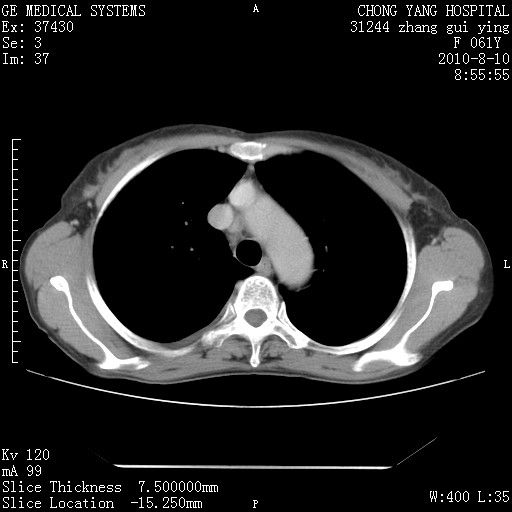

标题: CT28314:F61Y胸部增强,发热咳嗽一周入院,后面的为一周前平 [打印本页]

标题: CT28314:F61Y胸部增强,发热咳嗽一周入院,后面的为一周前平

1、支持考虑右侧中央型肺癌伴右肺中叶节段性不张及下叶支气管黏液痰栓    2、左肺上叶舌段感染。

支持3楼意见,还要考虑:纵隔及肺门淋巴结转移、右侧少量胸腔积液。

确切的说:1:右肺下叶中心型肺癌侵及中叶支气管并中叶不张,纵膈淋巴结转移。2:左肺舌叶炎症。3:右侧胸腔少量积液

块影平扫32hu,动静脉期62-70hu.